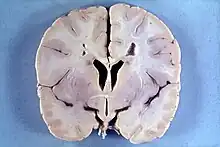

A doença de Alexander é uma doença genética extremamente rara, normalmente de aparecimento na infância e pertencente ao grupo das leucodistrofias.[1][2][3] Este grupo de doenças neurológicas caracteriza-se pela destruição progressiva da substância branca do cérebro. A doença de Alexander manifesta-se pelo aparecimento de atraso mental e anormalidades físicas, em especial macrocefalia, pela presença de fibras de Rosenthal e padrões de neuroimagem característicos. A doença progride até um desvincule mortal na maior parte dos casos. Ela recebeu seu nome do patólogo neozelandés William Stuart Alexander, que descreveu a síndrome em 1949, junto com a professora Dorothy Rusell no London Hospital. A Doença de Alexander foi descrita em 1949 e até 2005 foram registrados apenas 55 casos.